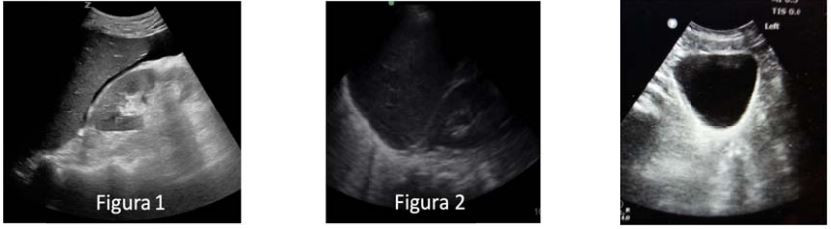

Homem, 21a, chega ao Pronto Socorro vitima de acidente motociclístico. Exame físico: Consciente orientado, PA = 117x78 mmHg, FC = 92BPM, FR = 16irpm, oximetria de pulso (ar ambiente) = 99%; Abdome: escoriações em parede anterior periumbilical. realizado FAST (focused assessment with sonografhy for trauma):

A INTERPRETAÇÕES DAS IMAGENS ACIMA: 1 (ESPAÇO HEPATORRENAL), 2 (ESPAÇO ESPLENORRENAL) E 3 (FUNGO DE SACO) SÃO, RESPECTIVAMENTE: